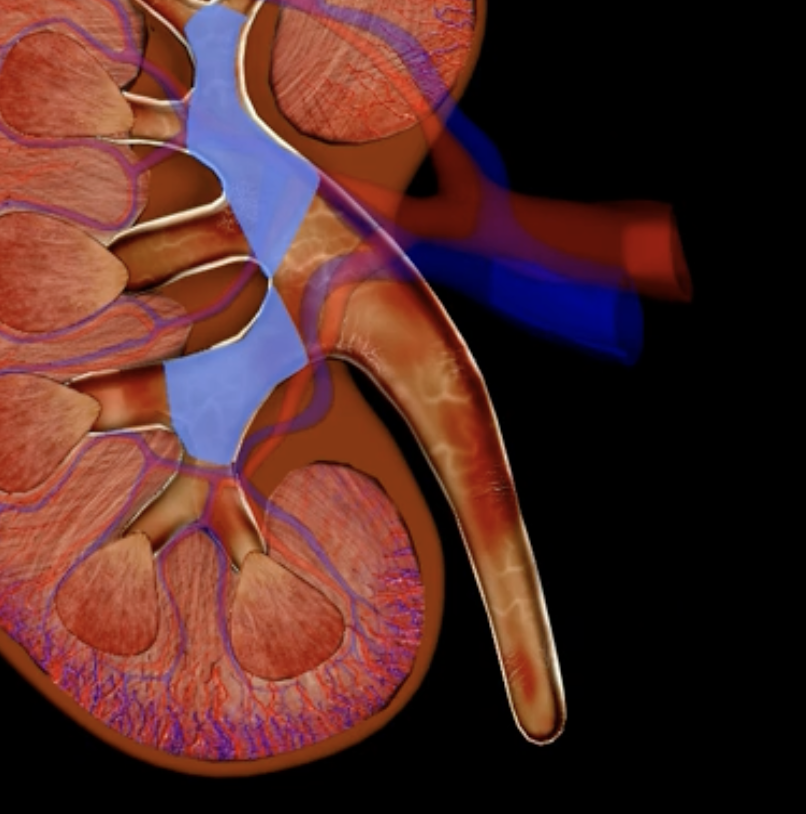

green: renal hilum

yellow: ureter

red: abdominal aorta

green yellow and red

renal pelvis

teal